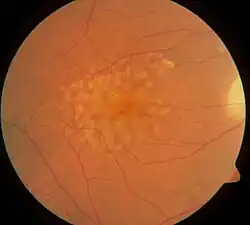

| Macular soft drusen in the right eye of a 70-year-old male. | |

Drusen, from the German word for node or geode (singular, "Druse"), are tiny yellow or white accumulations of extracellular material that build up between Bruch's membrane and the retinal pigment epithelium of the eye. The presence of a few small ("hard") drusen is normal with advancing age, and most people over 40 have some hard drusen.[1] However, the presence of larger and more numerous drusen in the macula is a common early sign of age-related macular degeneration (AMD).